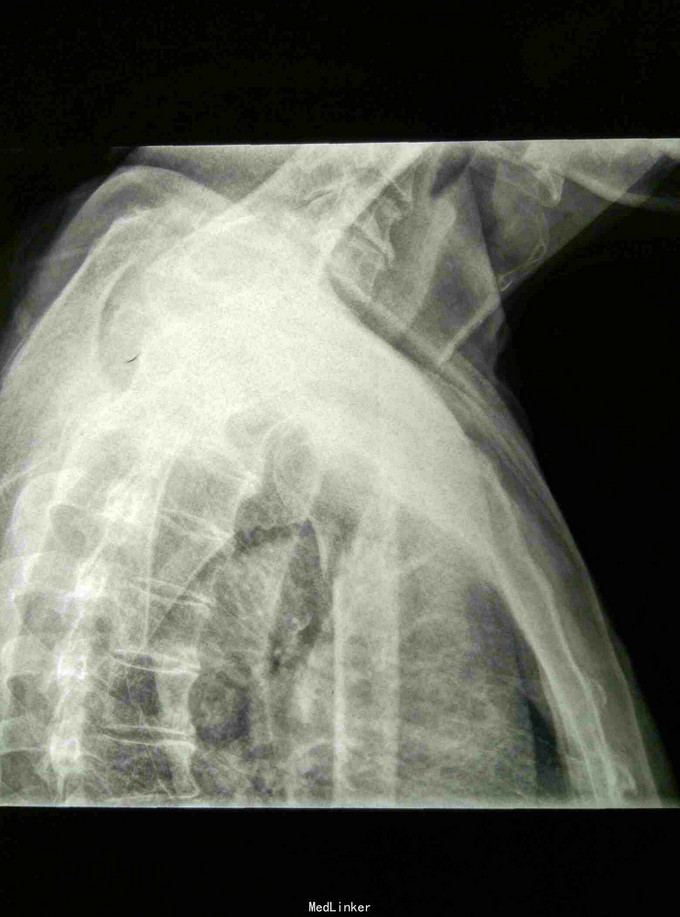

患者男60岁。主诉:左肩刺痛,活动受限2小时。 病史:患者2小时前散步时不慎摔倒,左肩刺痛, 活动受限。伤后由朋友送入我院。

左肩部畸形、肿胀明显,外科颈部压痛阳性,左肩部功能障碍。DR: 左肱骨近端粉碎骨折,分解为四部分,移位明显。

诊断:左肱骨近端粉碎骨折 治疗:手法整复,夹板固定。接骨丹口服。

随访1年。此四部分骨折,肱骨近端四个解剖部分完全分离,肱骨头移向后方,肱骨头血运破坏严重,容易发生缺血坏死。